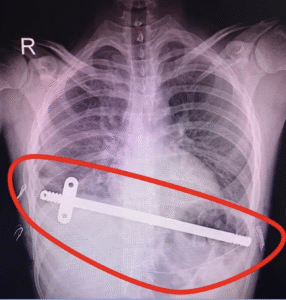

Flare Buster Technique is a technique that we perform during MIRPE or MIRPC surgeries by placing steel wires during surgery in order to remove some rib protrusions, especially rib flare deformity, which had been present in the patient before the surgery or may occur while the surgery.

Flare Buster Technique is applied in conjunction with MIRPE or MIRPC surgeries when deemed necessary by your doctor, and is terminated when the steel wire is removed while the bars are removed.